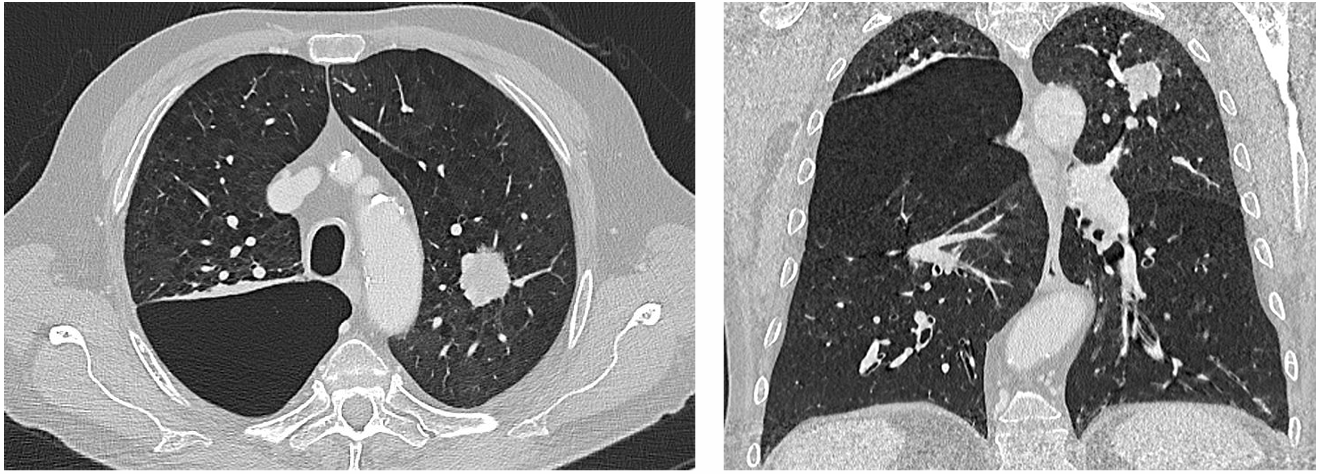

影像学评估

CT:左肺上叶尖段25mm结节,毛刺征阳性;双肺弥漫性肺气肿;右上肺巨大肺大疱(10.7cm),局部压迫邻近组织。

FDG-PET/CT(2022-11-11):结节SUVmax为5.8,未见淋巴结或远处代谢异常。